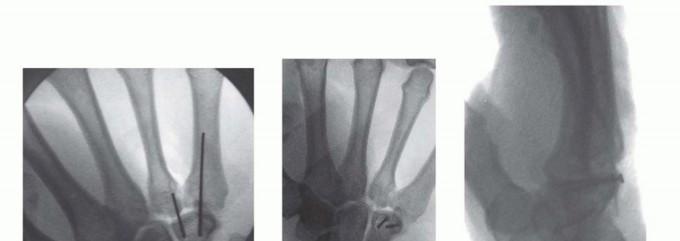

Hamate Hook Excision and Open Reduction Internal Fixation

Surgical intervention for the hamate hook is dictated by the chronicity of the injury and the size of the fracture fragment. For acute, large-fragment fractures at the base of the hook, Open Reduction and Internal Fixation (ORIF) is preferred to restore the biomechanical pulley of the flexor tendons. A volar approach is utilized, initiating the incision along the proximal thenar crease and extending it proximally across the wrist flexion creases in a zig-zag fashion to prevent scar contracture. The superficial palmar fascia is incised, and Guyon's canal is systematically explored. The ulnar nerve and artery are meticulously identified, mobilized, and protected with vessel loops throughout the procedure.

Image

For ORIF, the fracture site is exposed by carefully elevating the hypothenar musculature originating from the hook. The fracture is reduced and provisionally held with a K-wire. A cannulated headless compression screw (typically 2.0mm or 2.4mm) is then advanced over a guidewire from the tip of the hook down into the body of the hamate. Fluoroscopy is critical to ensure the screw does not penetrate the articular surface of the hamate body or impinge upon the CMC joints.